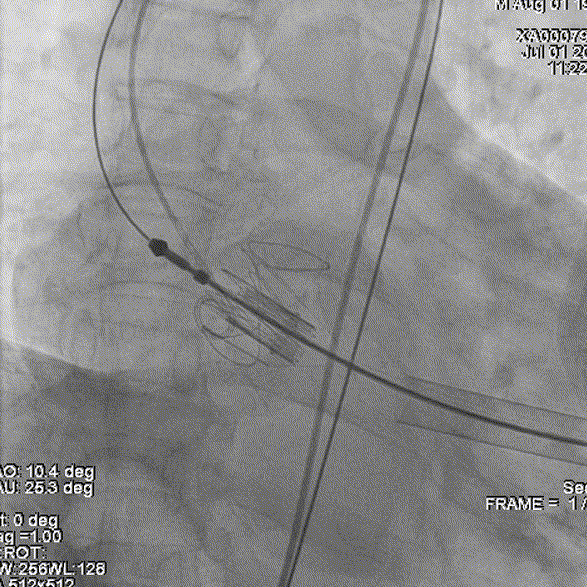

将瓣膜件降至瓣环平面,造影下定位:

释放J-valve29#瓣膜: